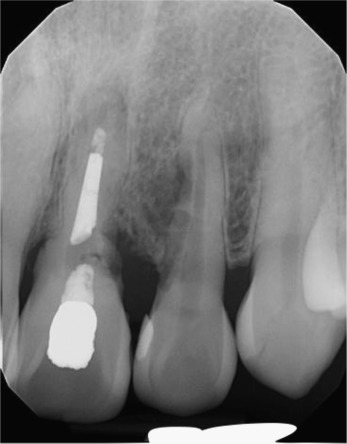

A twenty-six year old male patient was referred for the management of the symptomatic maxillary left central and lateral incisors. The incisors were diagnosed with external root resorption due to history of trauma. The long-term endodontic prognoses were assessed to be poor (Figs. 1 a, b and 2 ).

Fig. 2.

Pre-operative periapical radiograph showing external root resorption of maxillary left central and lateral incisors.